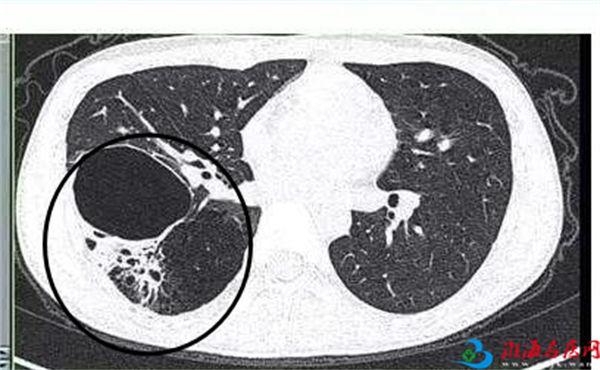

在小儿胸腔疾病方面,70%到80%都可以用胸腔镜来解决问题。如小儿漏斗胸、肺囊腺瘤、膈疝、隔离肺,以及纵膈的肿瘤,都可以用胸腔镜手术解决。